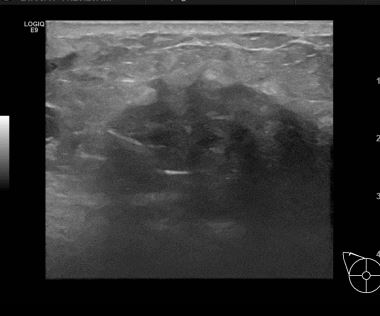

상기환자는 외부검진이상소견으로 내원하신 60대초반

여성분으로 의심스러운 우측혹 조직검사 시행해 침윤성암 으로 진단되었습니다